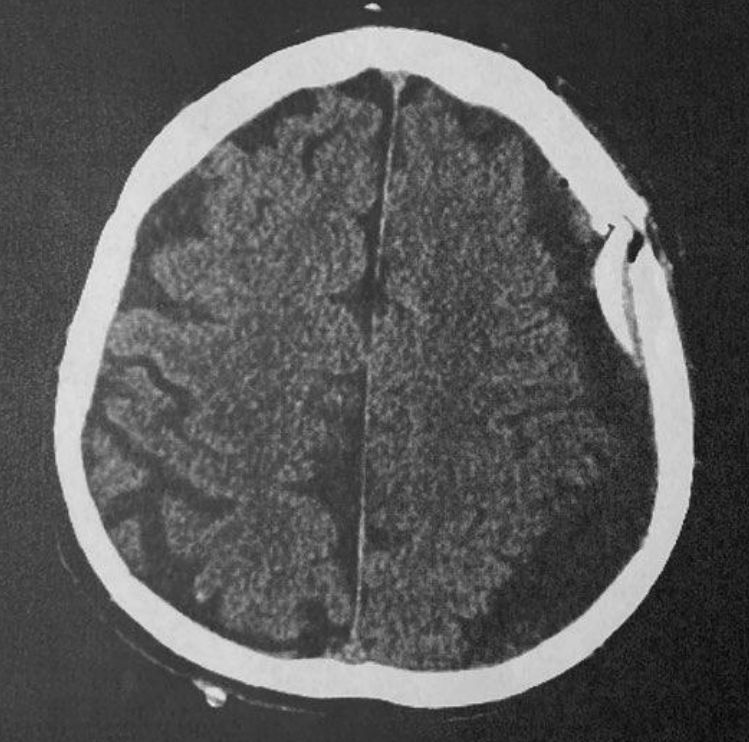

Als Folge hat er dann einen in der Verantwortung des Univ. Prof. Dr. Michael Mokry und Dr. Katharina Rauch inhaltlich medizinisch falsch erstellten ärztlichen Entlassungsbrief erhalten, der Kurzarztbrief ist ebenso falsch erstellt, in dem eine bestehende 1 cm breite 12 cm lange Hirnblutung nach Operation verheimlicht ist und in welchem steht, dass keine Raumforderungen mehr gegeben sei, also kein Blut mehr dort und das Hirn nicht mehr gequetscht sei, was, wie sich aus dem postoperativen cCT kurz vor, am Tag der Entlassung aus dem Spital ergibt objektiv falsch ist, da das gequetschte Hirn, eindeutig auch für einen Laien, wenn ihm dieses Bild gezeigt wird, erkennbar ist.